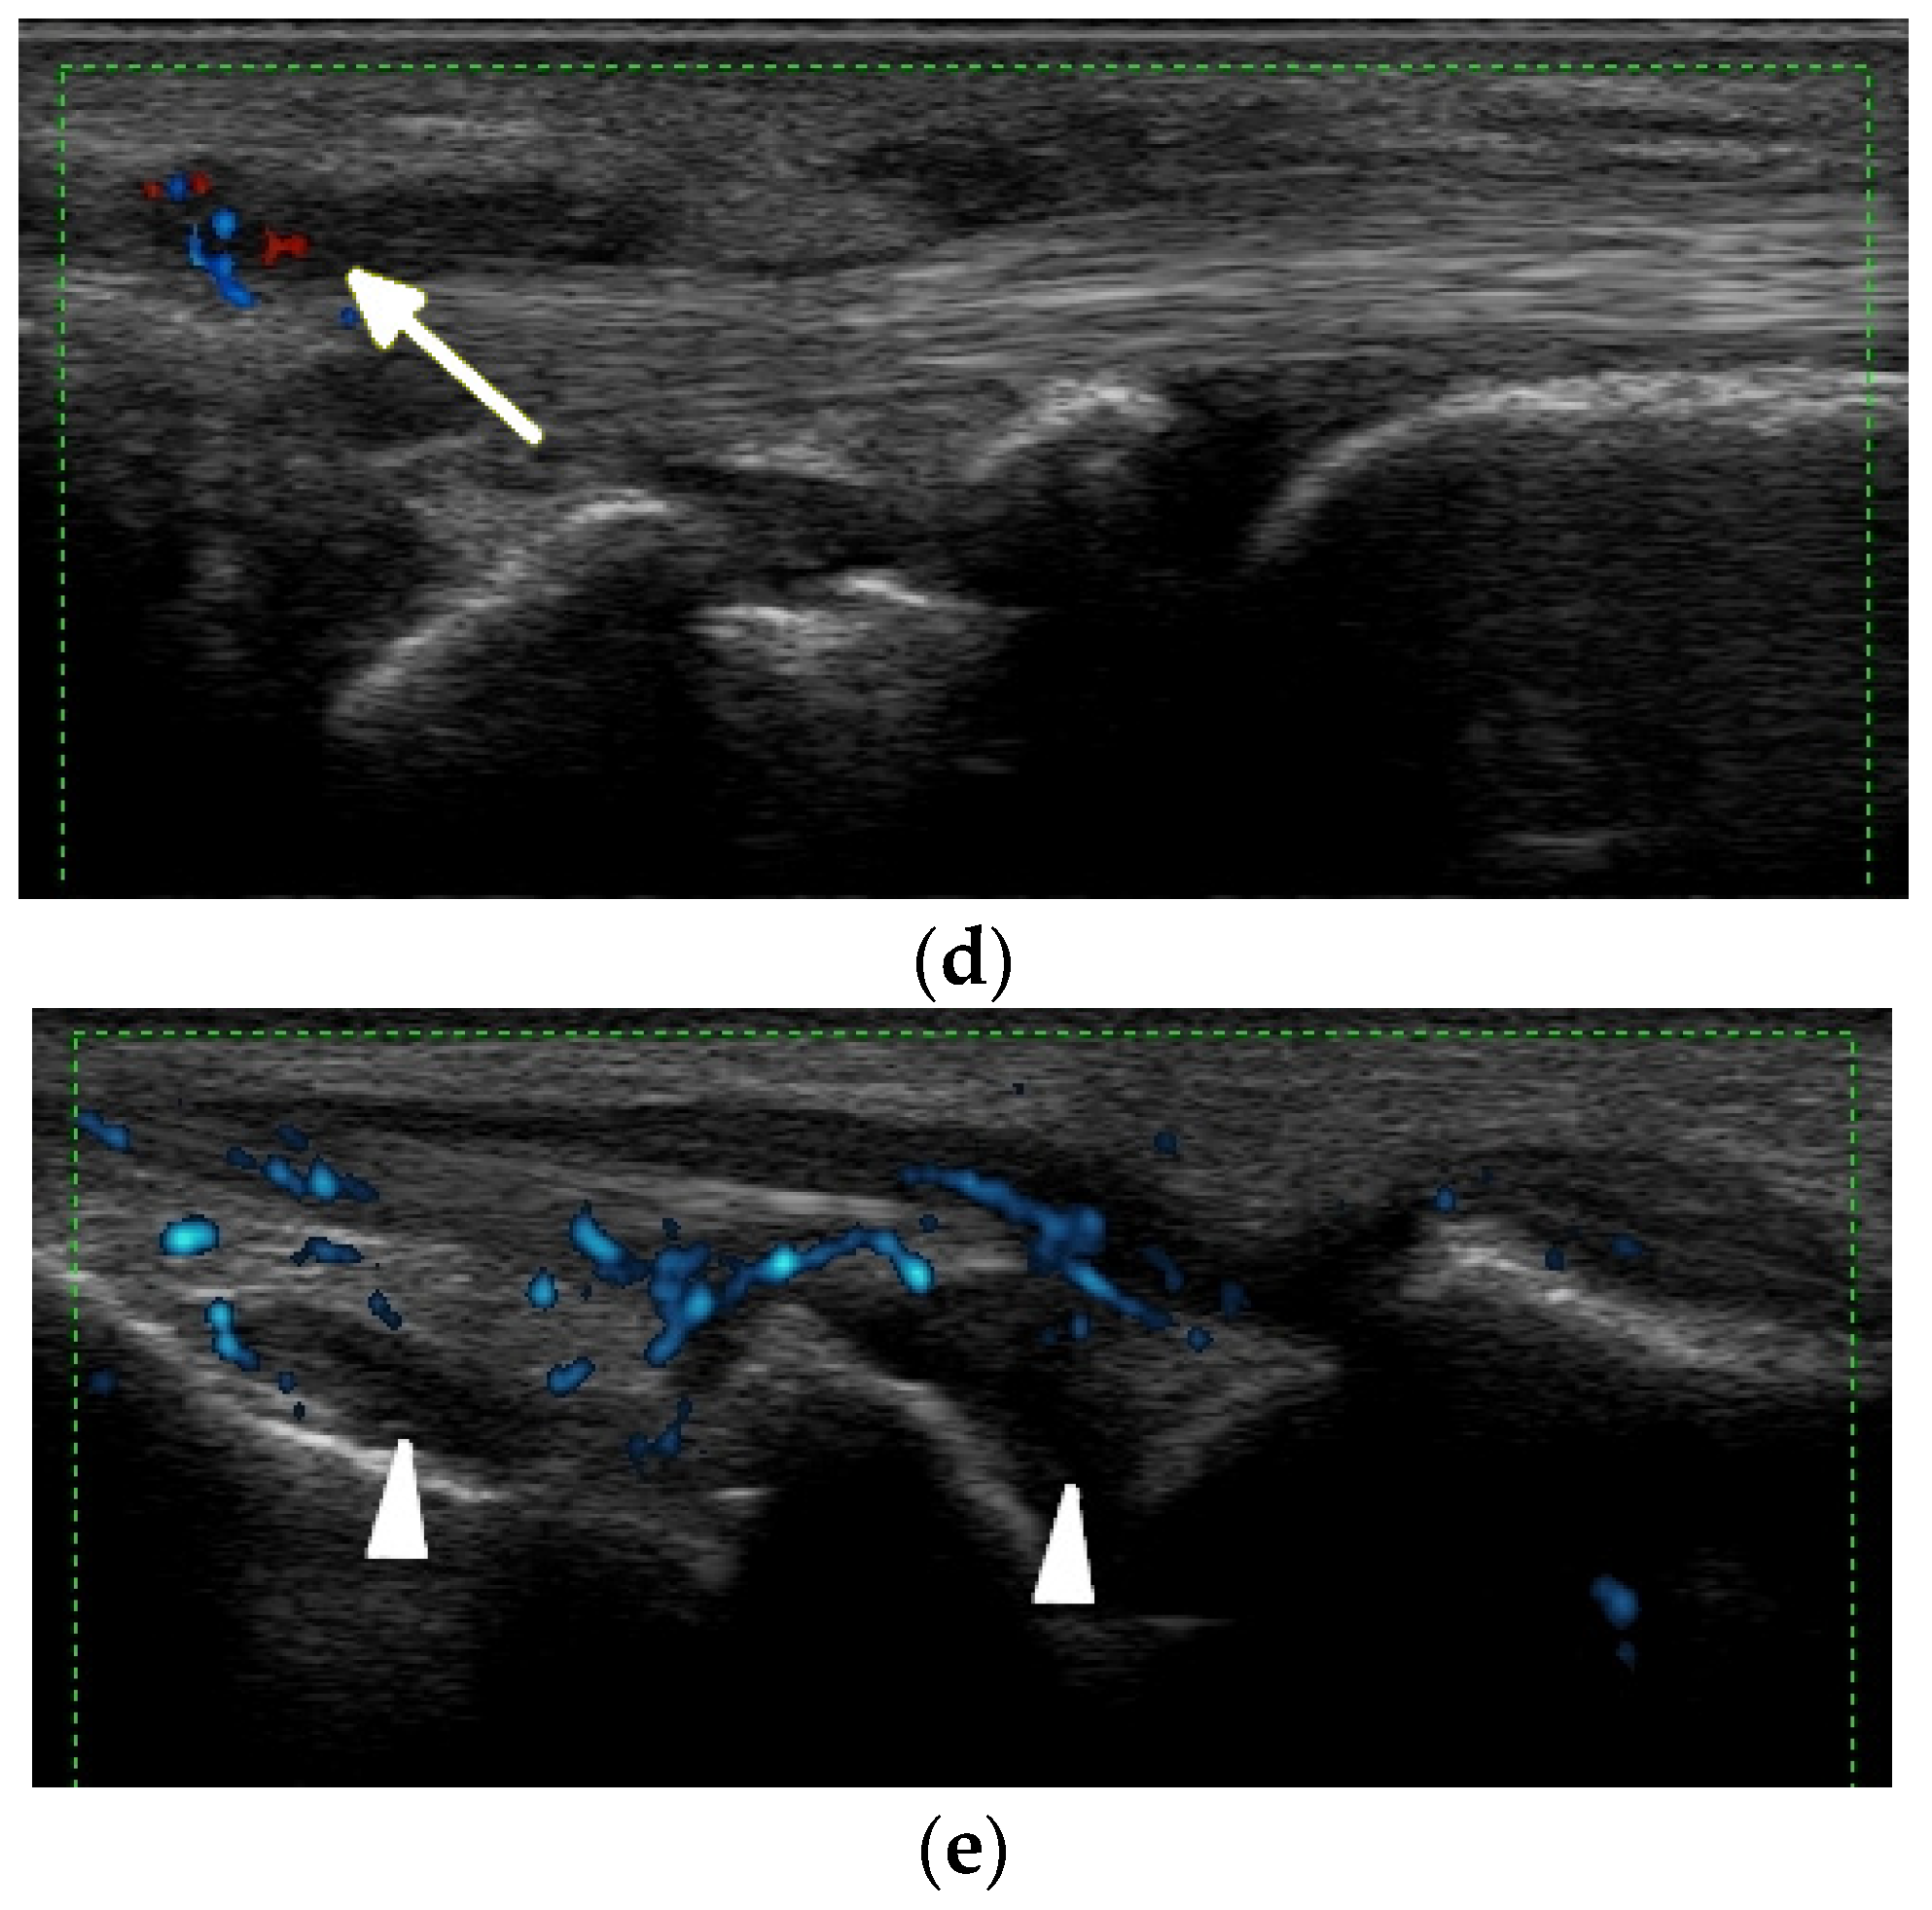

Figure 5.

A 57-year-old patient with systemic lupus erythematosus. (a) Short-axis power Doppler and (b) superb micro-vascular imaging (SMI) ultrasound (US) images of the distal radioulnar joint. (c) Long-axis power Doppler and (d) SMI US images at the dorsal aspect of the radiocarpal and midcarpal joints show joint effusions and hyperemia consistent with synovitis with more vessels seen with SMI (b,d). Note an intra-osseous cyst-like change (short arrow) and cortical erosion (long arrow in (d)) in the carpal bone related to rhupus syndrome.